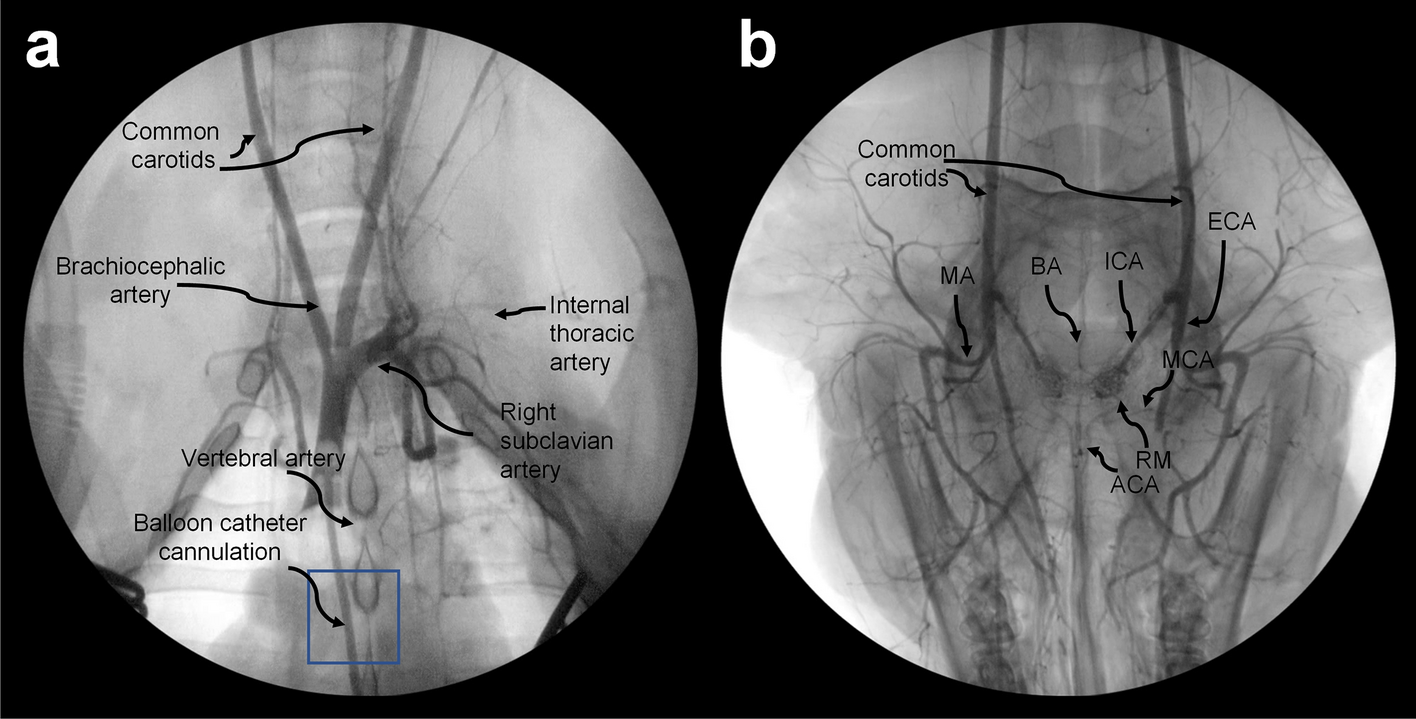

Arterial angiograms of chest and head. Thoracic angiogram obtained via brachiocephalic cannulation (a) and extension of the radiographic field to the head (b) to illustrate the arteries derived from the carotids. The position of the balloon catheter is indicated in (a) with a box. The usual craniocaudal orientation is reversed in (b), with the snout pointing toward the inferior part of the image. MA: mandibular artery; BA: basilar artery; ICA: internal carotid artery; ECA: external carotid; MCA: middle cerebral artery; ACA: anterior cerebral artery; RM: rete mirabile.